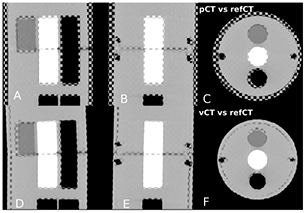

Standard image High-resolution imageFigure 3. (a)–(c) Checkerboard comparison of the pCTCBCT and refCTCBCT. (d)–(f) Comparison of the vCTCBCT and refCTCBCT.

Figure 4 presents the results of the aSIFT evaluation for the 6 possible image inter-comparisons using Tz = 6 mm. We observed that the median distance between corresponding features was lowered when comparing the vCTCBCT, refCTCBCT and CBCTCBCT together, indicating that our registration algorithm yielded a vCTCBCT which agreed better with the CBCTCBCT/refCTCBCT than the pCTCBCT. The median distances are of the order of 2–3 mm, which is comparable to the planning CT resolution of 1.074 mm in the axial plane and 3 mm in the scan direction. Interpolating the CT to the CBCT coordinate system does not improve its resolution, however the fact that the phantom is homogenous in the Z direction means that for homogeneous parts of the phantom this interpolation should yield similar values as a higher resolution reconstruction. This is however not true at edges, where most features are detected. It is thus likely that our results are limited by a combination of the precision of the aSIFT algorithm and the slice thickness used. The median feature distances for the vCTCBCT versus refCTCBCT and pCTCBCT versus refCTCBCT comparisons are reported in table 3 before and after outlier removal. A Wilcoxon rank sum test between the feature distances of the vCTCBCT versus refCTCBCT and pCTCBCT versus refCTCBCT after outlier removal yielded p < 0.01. The aSIFT algorithm yielded matching features between the vCTCBCT and refCTCBCT/CBCTCBCT which exhibited large differences in their Z positions, hence the need for a Tz rejection. This is illustrated in figure 5 where accepted and rejected features are shown.

Standard image High-resolution imageFigure 6 presents the results of the aSIFT evaluation between the pCTCBCT versus refCTCBCT and vCTCBCT versus refCTCBCT for all configurations. As expected configuration 3 shows the largest difference between pCTCBCT and vCTCBCT, however the vCTCBCT shows lower median feature distances than the pCTCBCT for configurations 1 and 2 as well.